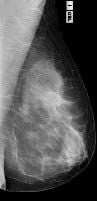

MamaTécnicas de Exploración Radiológica Imágenes mamográficas 8 agosto, 2012 Tidito Clasificacion de una mama normalCasi enteramente compuesta por tejido adiposo (Grasa).Con componente fibroglandular dispersoHeterogéneamente diensaExtremadamente densaProyecciones Cráneo Caudales Proyecciones Oblicuas